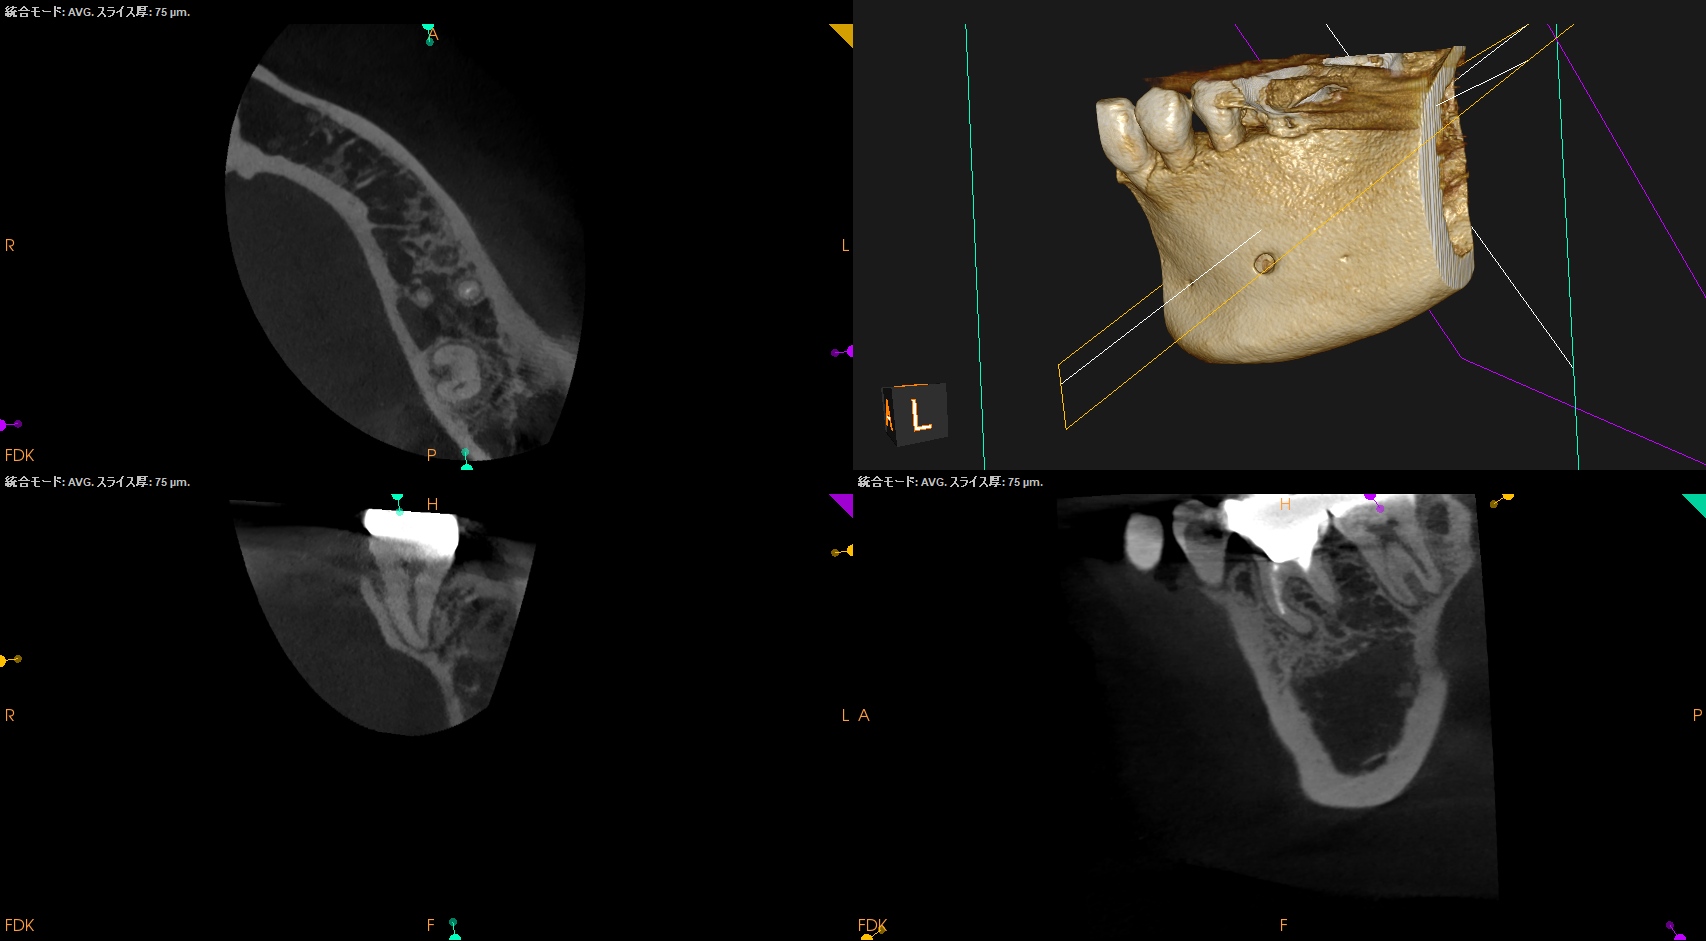

CBCTも撮影した。

#18 MB

#18 D

が、PAやパノラマで見られたような初見はCBCTでは得られなかった。

むしろ、近心根の根尖部に病変があるように見える。

ともあれ、#18は樋状根であるということがわかる。

術後にPA,CBCTを撮影した。